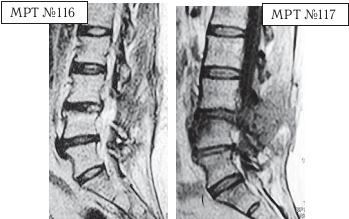

После операции у данной пациентки боли в ноге не уменьшились. Но зато добавились боли в поясничном отделе позвоночника. Оперировавший её хирург пояснил, что после операции на позвоночнике боли могут присутствовать ещё длительное время, что необходимо принимать лекарства и постепенно воспаление спадёт и всё будет хорошо. Но «хорошо» в течение трёх месяцев так и не наступило, а вот боли усилились, и лекарства практически уже не действовали. Для того чтобы разобраться в причинах, вызывающих эти боли, повторно сделали МРТ.

На МРТ № 116 (в режиме Т2-ВИ) и МРТ № 117 (в режиме Т1-ВИ) той же пациентки наблюдается состояние через три месяца после хирургического вмешательства.

На МРТ № 117 в режиме Т1-ВИ отчётливо видно, что был прооперирован межпозвонковый диск в сегменте LIII—LIV вместо диска в сегменте LIV-LV В передней части тела позвонка LIV наблюдается очаг воспаления, реактивный асептический дисцит (частая и можно сказать естественная реакция тканей на операцию, вследствие развития аутоиммунных реакций).

Нейрохирург, ознакомившись с результатами обследования МРТ и увидев, что произошла ошибка (был прооперирован не тот межпозвонковый диск), настоял на проведении ещё одной операции. Естественно, пациентка не хотела идти на вторую операцию на позвоночнике, так как уже была напугана результатами первой операции. Однако лекарства не помогали, а боли, по её словам, «просто сводили с ума». В общем, она согласилась на повторную операцию.